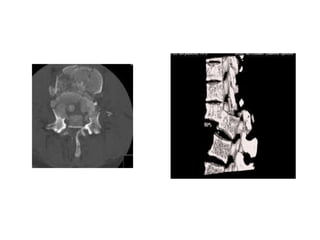

CT Scan

• Accurate assessment

of bone.

1- Comminution.

2- Canal compromise.

3- Dislocation.

CT Scan • Accurateassessment of bone. 1- Comminution. 2- Canal compromise. 3- Dislocation.